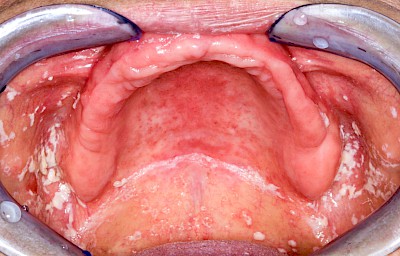

Pilzerkrankung

Pilze gehören zur physiologischen Mundflora und sind grundsätzlich nicht problematisch. Schlechte Mund- bzw. Prothesenhygiene und ggf. gleichzeitig übermäßiger Verzehr kohlenhydratreicher Nahrung kann das Pilzwachstum jedoch begünstigen Der typische Pilz im Mund ist Candida albicans, ein sprossbildender Hefepilz. Bei übermäßigem Pilzwachstum spricht man von einer Pilzerkrankung, Pilzfinfektion, Pilzbefall, Soor oder Candidose. Pilzerkrankungen können auch im Fall guter Mundhygiene auftreten bei:

Wenn die Intensivierung der Mundpflege allein den Pilzbefall nicht zu verhindern vermag, sind in manchen Fällen dann zusätzliche Maßnahmen wie Medikamente gegen Pilze (Antimykotika) nach ärztlicher Rücksprache angezeigt.

Beispiele25 Bilder